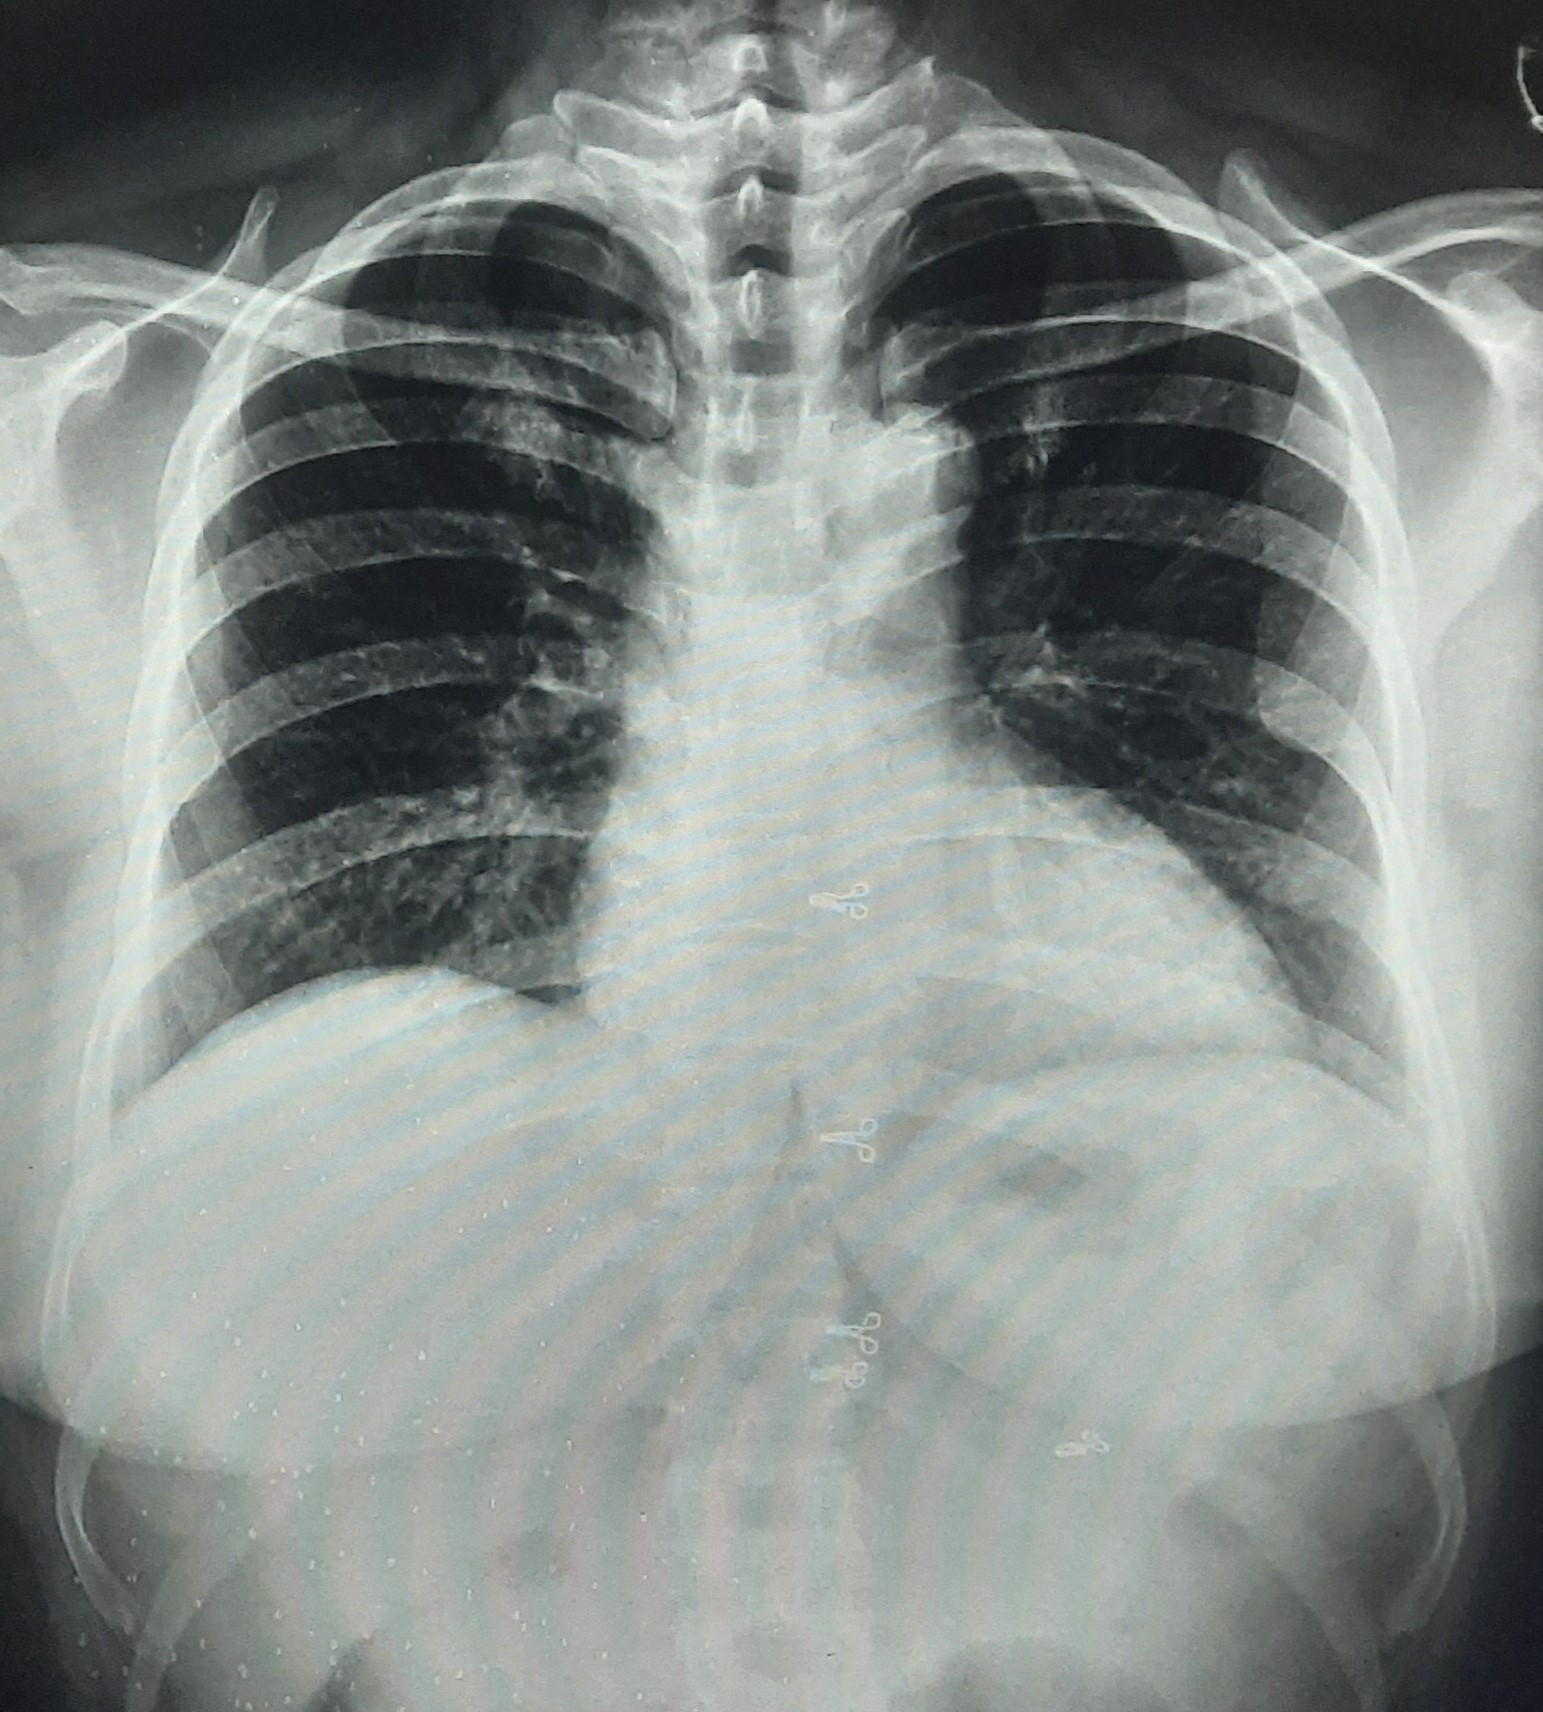

| 331 | IGGMC, Nagpur, Nagpur | P2 | 29-4141 | Madhukar Fulake | Consent taken on Paper | 55 Yrs. |

Provisional Diag : Post TB Sequelae, Fibrosis

Final Diag : Post TB sequalae, COAD With Left Sided Pleural Parenchymal Fibrosis With Left Sided Plural Calcification With Faty Liver |

Post TB Sequelae | Abnormality visible on x-ray |